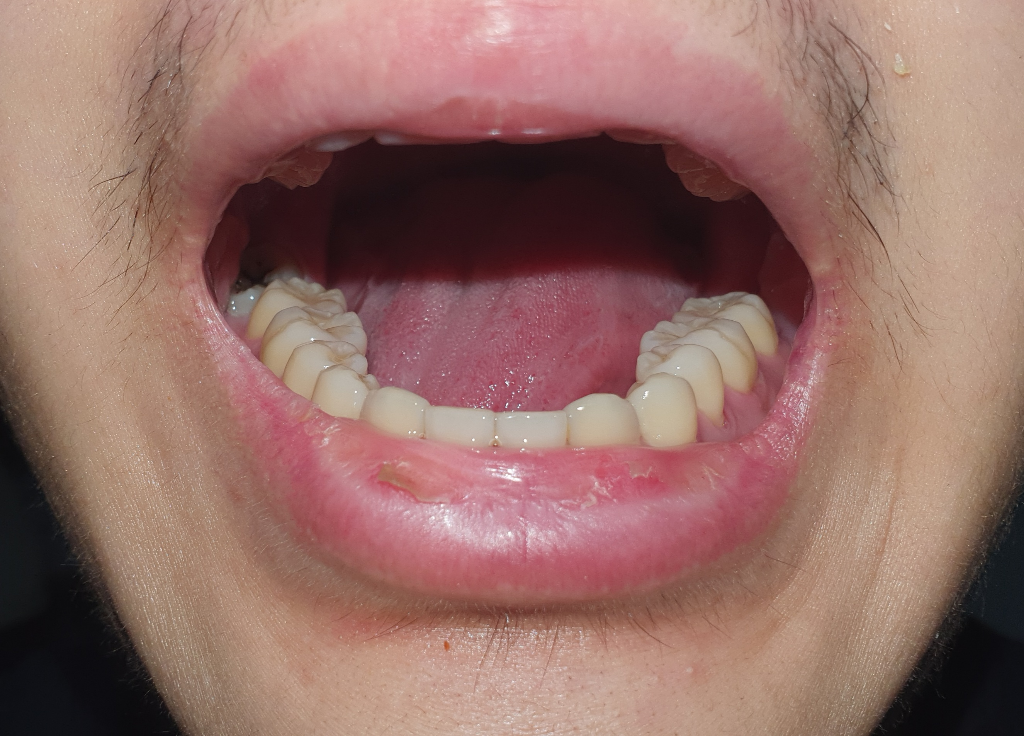

교합이 기울어졌는데 어떻게 해야 될까요?

성인인 현재 하악이 기울어지고 (어금니가 기울어진것 같기도 합니다) 전체적인 안면비대칭이 심합니다 지금 시험을 준비하고 있어서 거리든 비용문제든 교정전문 치과를 당장 다니기는 힘든 상황입니다 그래서 1년뒤에나 교정할수 있을 것 같은데

두꺼운거 씹으면 위로 올라간 쪽 하악에서 살ㅡ짝 덜컥하는 느낌이 듭니다 (입 벌어지고 모래 소리 안남)

개방교합 있고요

맨밑 사진은 사랑니 발치전 2년전 사진이라 교합이 좀 다를 수 있습니다